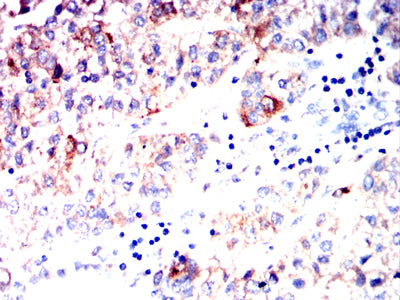

- Immunohistochemical analysis of paraffin-embedded human liver cancer tissues using AFP mouse mAb with DAB staining.